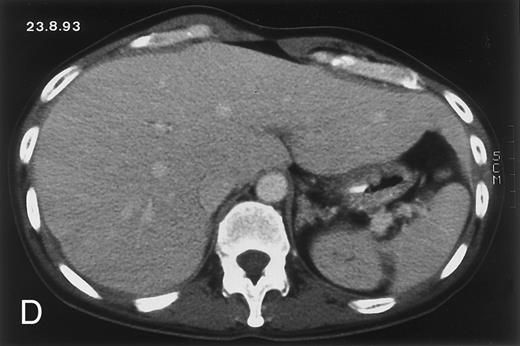

(D) On August 23, 15 days after the neutrophil count had dropped below 500/μL in the third chemotherapy cycle, focal liver lesions clearly decreased in size and number. (E) On September 30, 35 days after neutrophil recovery, multiple hepatic abscesses are seen (arrowhead). To show maximal extent of lesions the scan shown is at a slightly different level. (F) On June 16, 1994, 230 days after neutrophil recovery, the CT scan has normalized.

Evolution of fungal lesions on CT scans during and after neutropenia is summarized in Table 2. Figure 1 (patient A) and Fig 2 (patient B) serve to illustrate Table 2.

In three patients, multiple round lesions were seen on postcontrast CT scans of the abdomen in the liver and the spleen, while in two cases, lesions could only be seen in the liver (Table 2). Following the diagnosis of disseminated candidiasis, these lesions decreased in size and visibility during subsequent neutropenia in three patients (compare Fig 2A and B) and disappeared completely in two patients (compare Fig 1A and B). The numbers of days of severe neutropenia (neutrophils <500/μL) at the time the CT scan was performed are listed in Table 2. After recovery from neutropenia and despite continued antifungal therapy, the size and visibility of the lesions increased again (Fig 1C). Similarly, the number of days since recovery from severe neutropenia (neutrophils >500/μL) are listed in Table 2. In two of three patients treated with another cycle of myeloablative chemotherapy, this waxing and waning pattern of radiologic lesions could be seen again (Fig 1D and E). In all patients, lesions eventually disappeared (Figs 1F and 2D) after prolonged antifungal therapy.